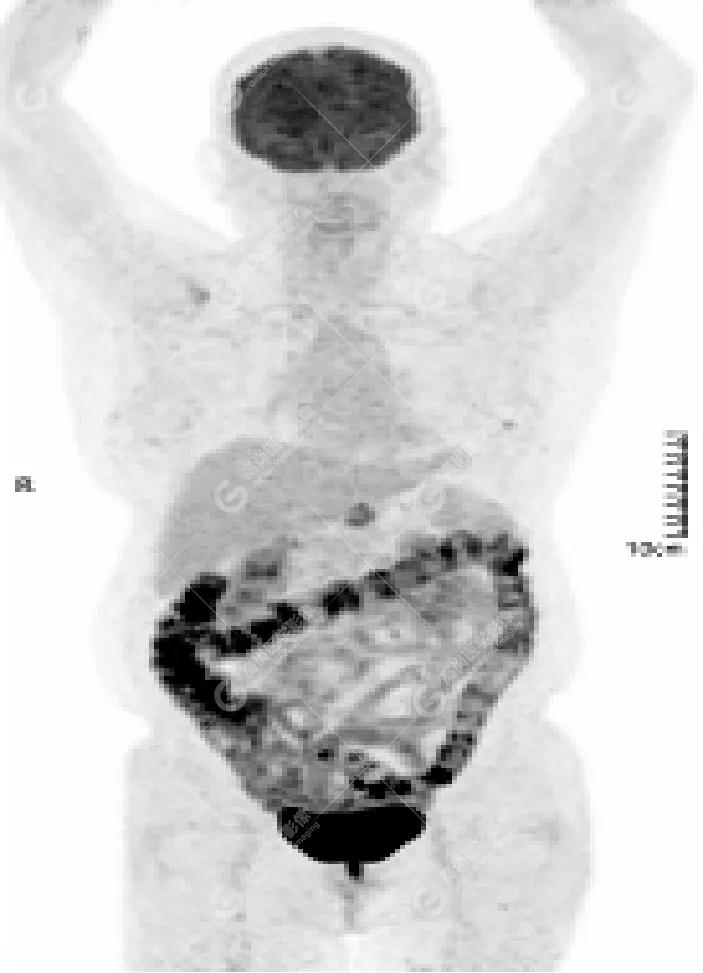

PET/CT

影像图

胸椎溶骨性骨质破坏,FDG环状代谢增高,SUVmax为4.0。

左侧乳腺一软组织结节,FDG代谢增高,SUVmax为2.6。

最终诊断: 左侧乳腺癌伴胸椎单发骨转移。